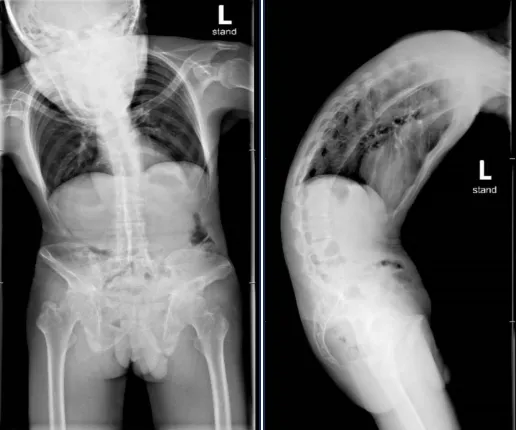

▲患者手术前脊柱正、侧位片